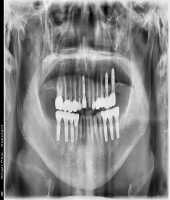

| ● 진료과목 : [임플란트] 틀니 사용중, 임플란트로 교체하기

| ● 내용 : 하악틀니 사용 중 불편감으로 임플란트로 교체한 예 |